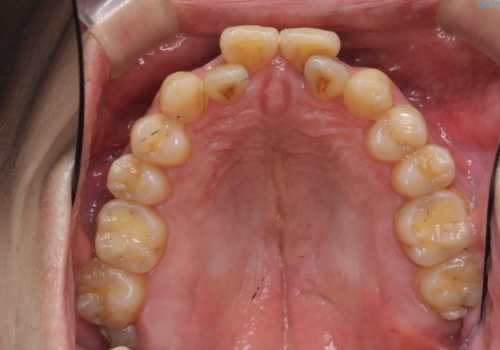

- 前歯の重なったところが虫歯になり、物理的にアプローチが難しい状態でした。

矯正治療前に虫歯を取り、歯並びが良くなってから本格的にセラミック治療を行いました。